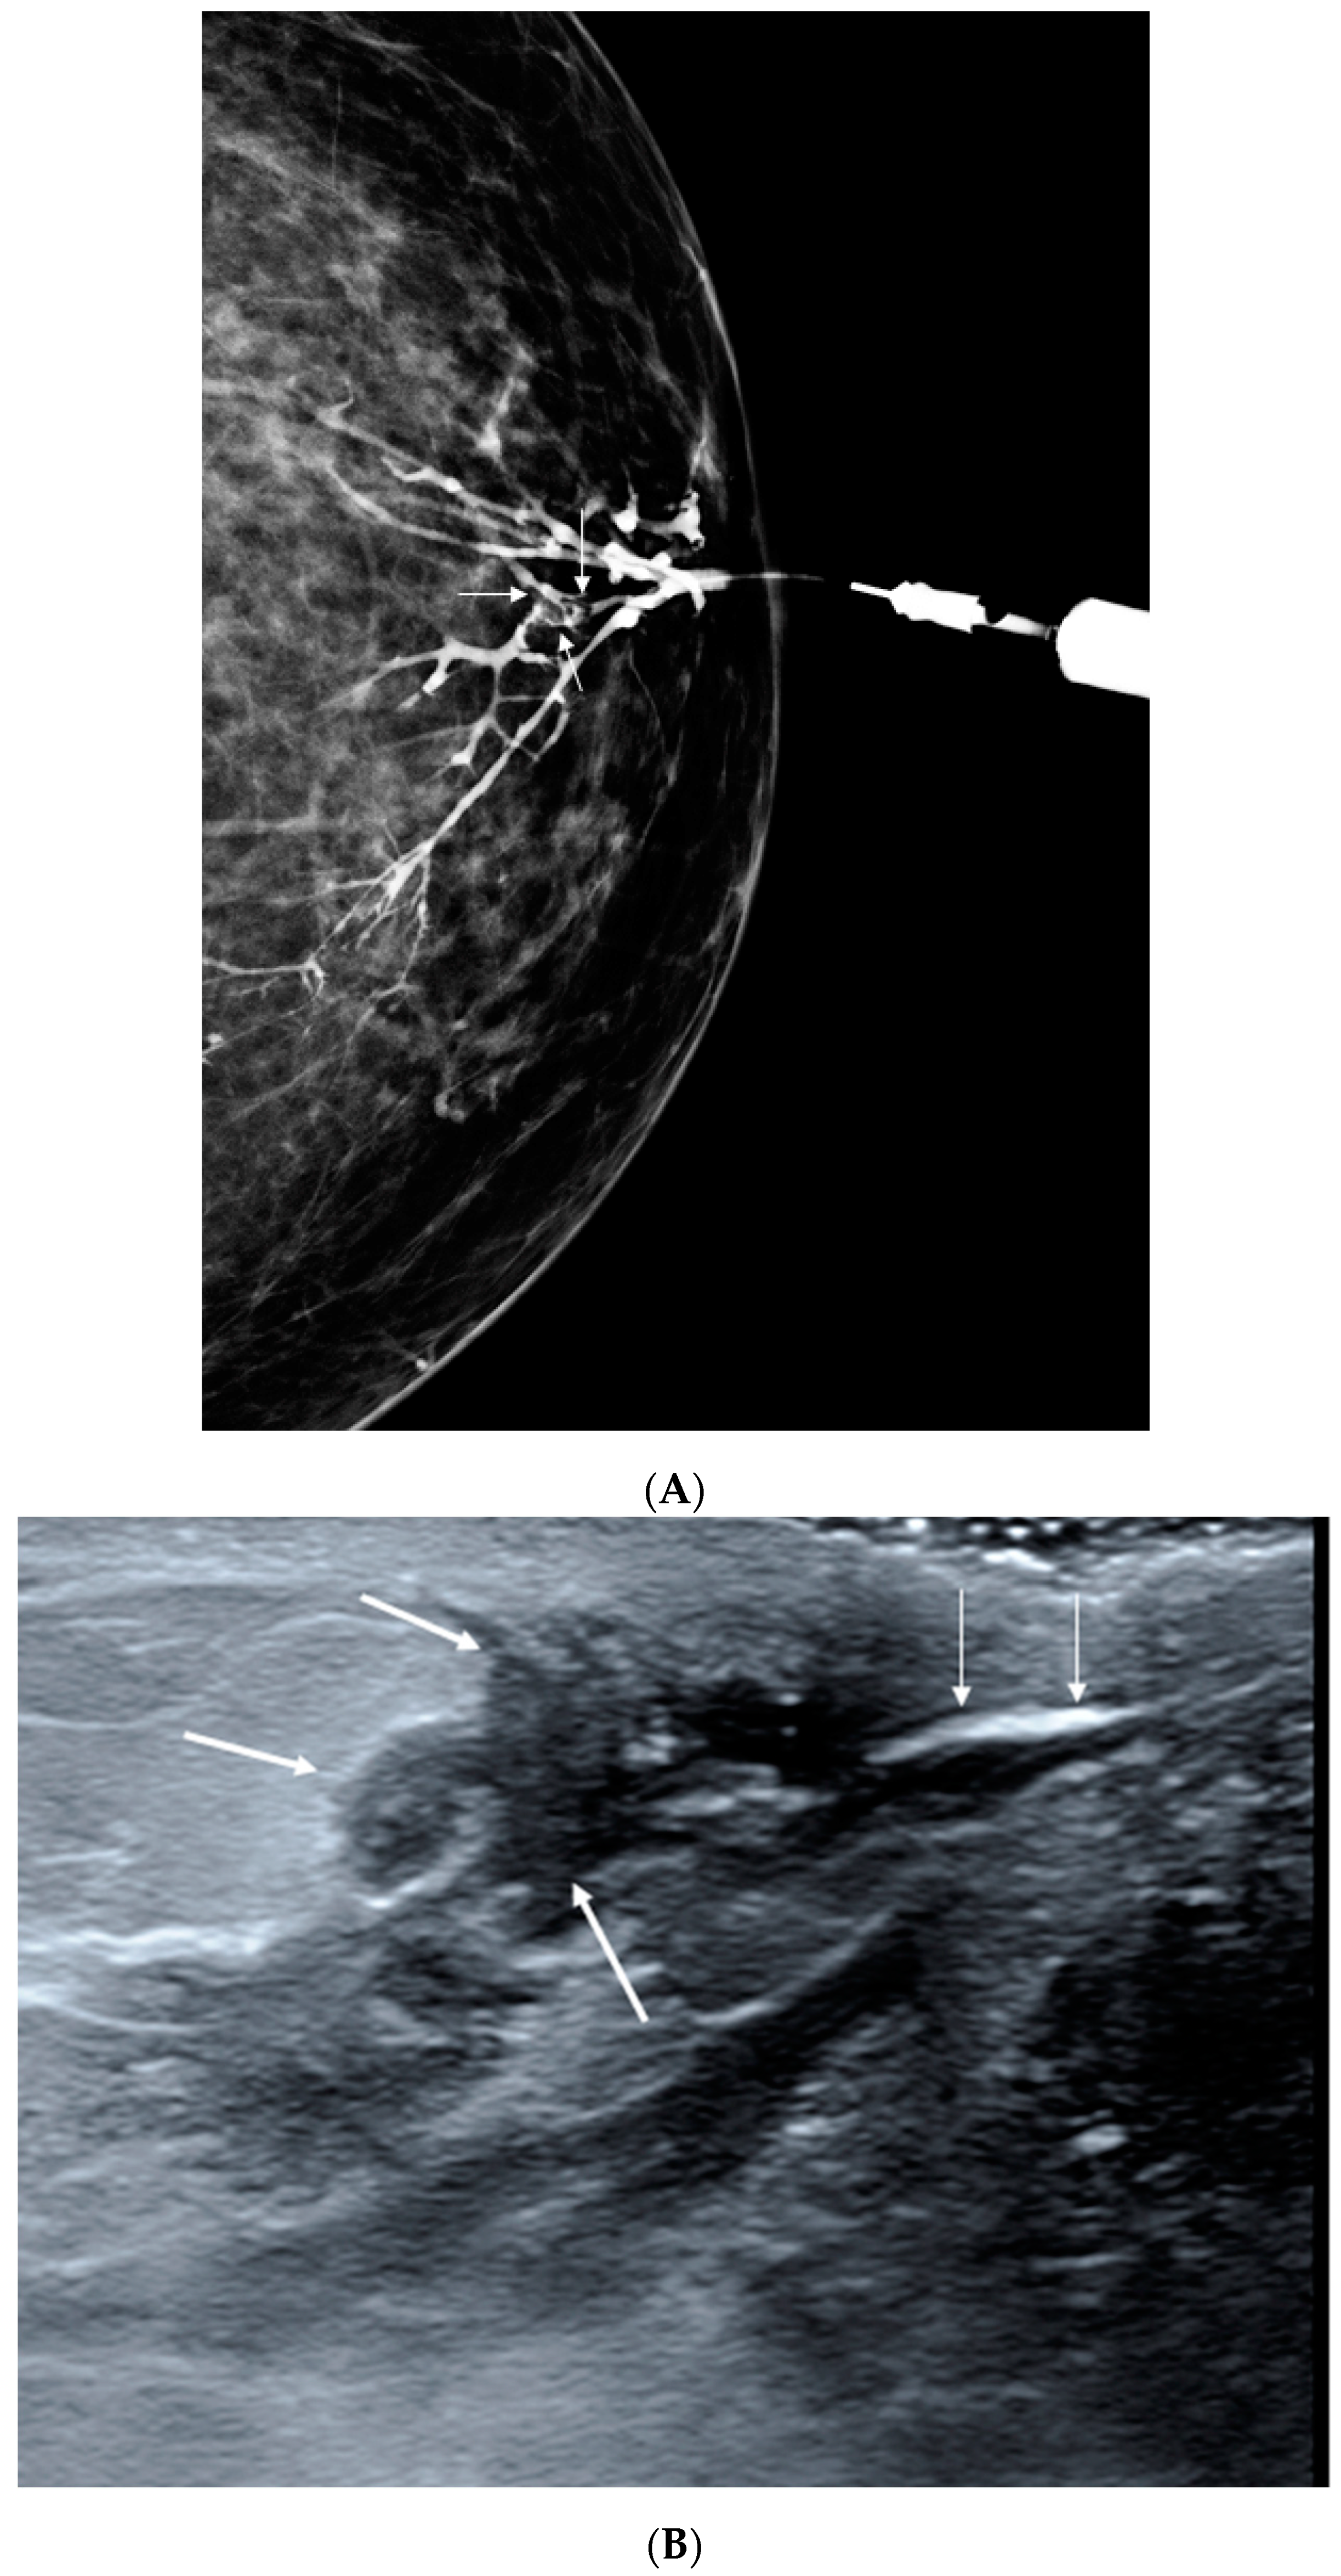

2.2. Galactography

2.3. Sonogalactography